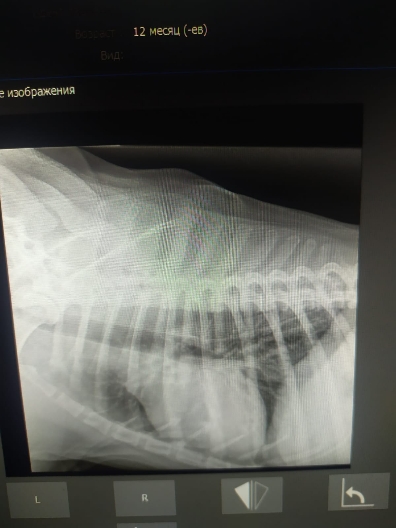

Рентген и анализы.

Рентген легких бы еще в другой позиции и на эхо к кардиологу сходить.

Просто на рентгене вопрос к форме сердца.... тогда может рентген на спине попозже